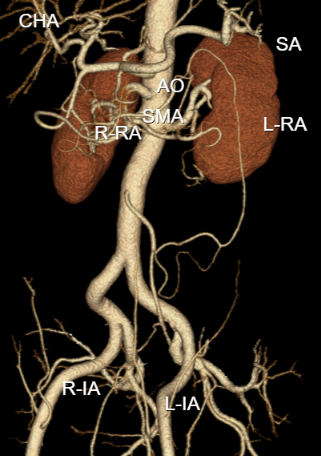

在多学科团队的全程监护下,患者迅速接受了腹部CTA检查,最终确诊为“急性孤立性肠系膜上动脉夹层”——这正是那个随时可能导致大范围肠坏死、腹腔大出血的“隐形杀手”。由于患者年轻且病情进展迅速,保住缺血肠道刻不容缓,多学科团队会商后,决定立即实施急诊介入手术。

手术室内,介入外科、介入诊疗中心团队迅速就位。在局部麻醉下,介入外科团队精准穿刺股动脉,DSA造影清晰显示了夹层破口位置,随着支架的精准植入,复查造影显示:肠系膜上动脉主干通畅,各分支动脉显影良好,被阻断的肠道血供得以恢复!患者腹痛随即明显缓解。从入院到血管再通,全程仅用4个多小时,成功守住了肠道耐受缺血的“黄金救治窗”。